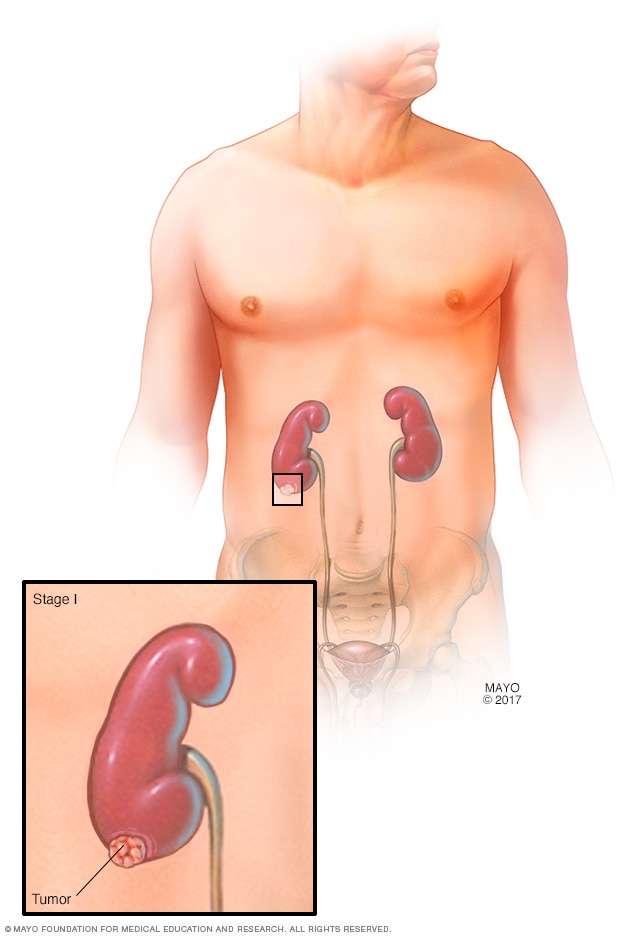

Stage 1 kidney cancer

A stage 1 kidney cancer means that the tumor in the kidney is 2 3/4 inches (7 centimeters) in diameter or smaller. The cancer is only in one kidney and completely contained within it.

The stages of kidney cancer range from 1 to 4. A stage 1 kidney cancer is small and confined to the kidney. As the cancer gets larger, the stages get higher. A stage 4 kidney cancer has grown beyond the kidney or spread to other parts of the body.